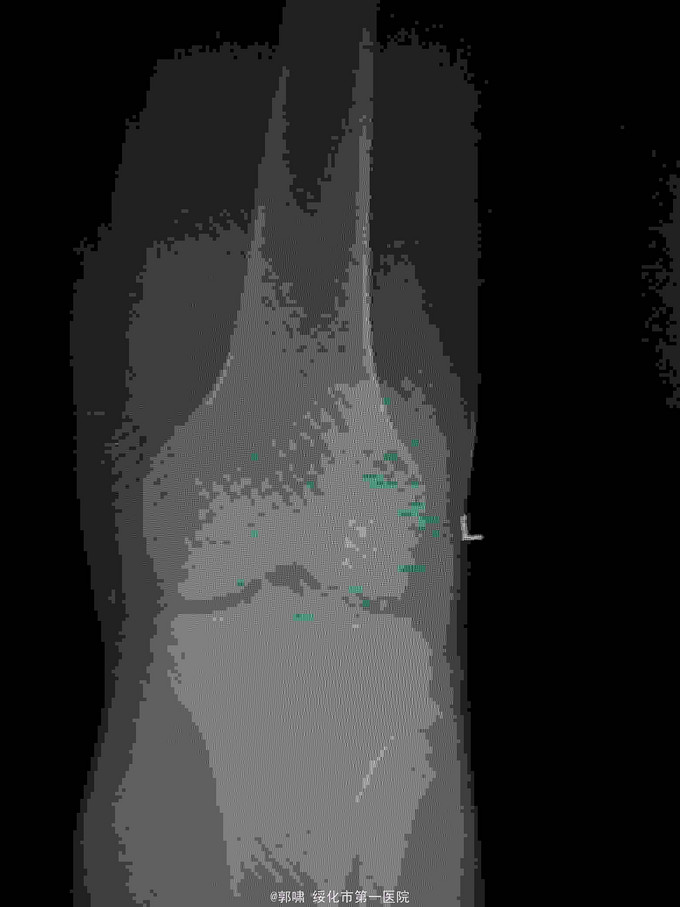

诊断:左髌骨骨折。立即予以腰麻下行切开复位内固定术。术中复位骨折,缝合筋膜,冰水浸泡髌骨爪约10分钟。待髌骨爪变软。选取合适大小的髌骨爪。应用记忆合金髌骨爪内固定。立即用40°温盐水热敷局部。使记忆合金加速抓紧。环抱。缝合爪齿二道,防止脱落。缝合关节囊,韧带组织。术毕。

应用记忆合金髌骨爪内固定髌骨骨折。手术时间基本在20----30分钟内都可以完成。局部损伤小。固定牢靠,确实。患者二个月就可以下地负重活动。具体手术技巧。一是髌骨爪提前用冰盐水侵泡10分钟左右。待记忆合金变软即可使用。二。固定牢靠后立即用40°温盐水热敷。使其快速抓紧。三,缝合爪齿,防脱。四如有粉碎,小的骨块可以缝合筋膜固定。有大骨块,最好环扎钢丝,或穿针固定,有时穿骨隧道钢丝捆扎。效果也不错。只要做到以上几点。安全无忧了!以下是以前做的片子。可以看一看。